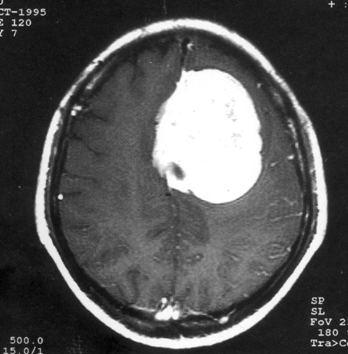

问题 病历摘要:??患者,男,40岁。发作性左下肢抽搐1年余,每次发作3~5分,每周发作1~2次。每次发作后感左下肢乏力,约半日后可自行恢复。既往身体健康。体检:神清,头顶部偏右有局限性骨性隆起(1.5×1.5cm),左鼻唇沟稍浅,伸舌居中。感觉、运动无明显异常。左浅反射减退,左下肢腱反射稍亢进,左Babinski征(-)。 术前的检查和治疗应包括下列哪些?提示:初步诊断考虑脑膜瘤,拟手术治疗。